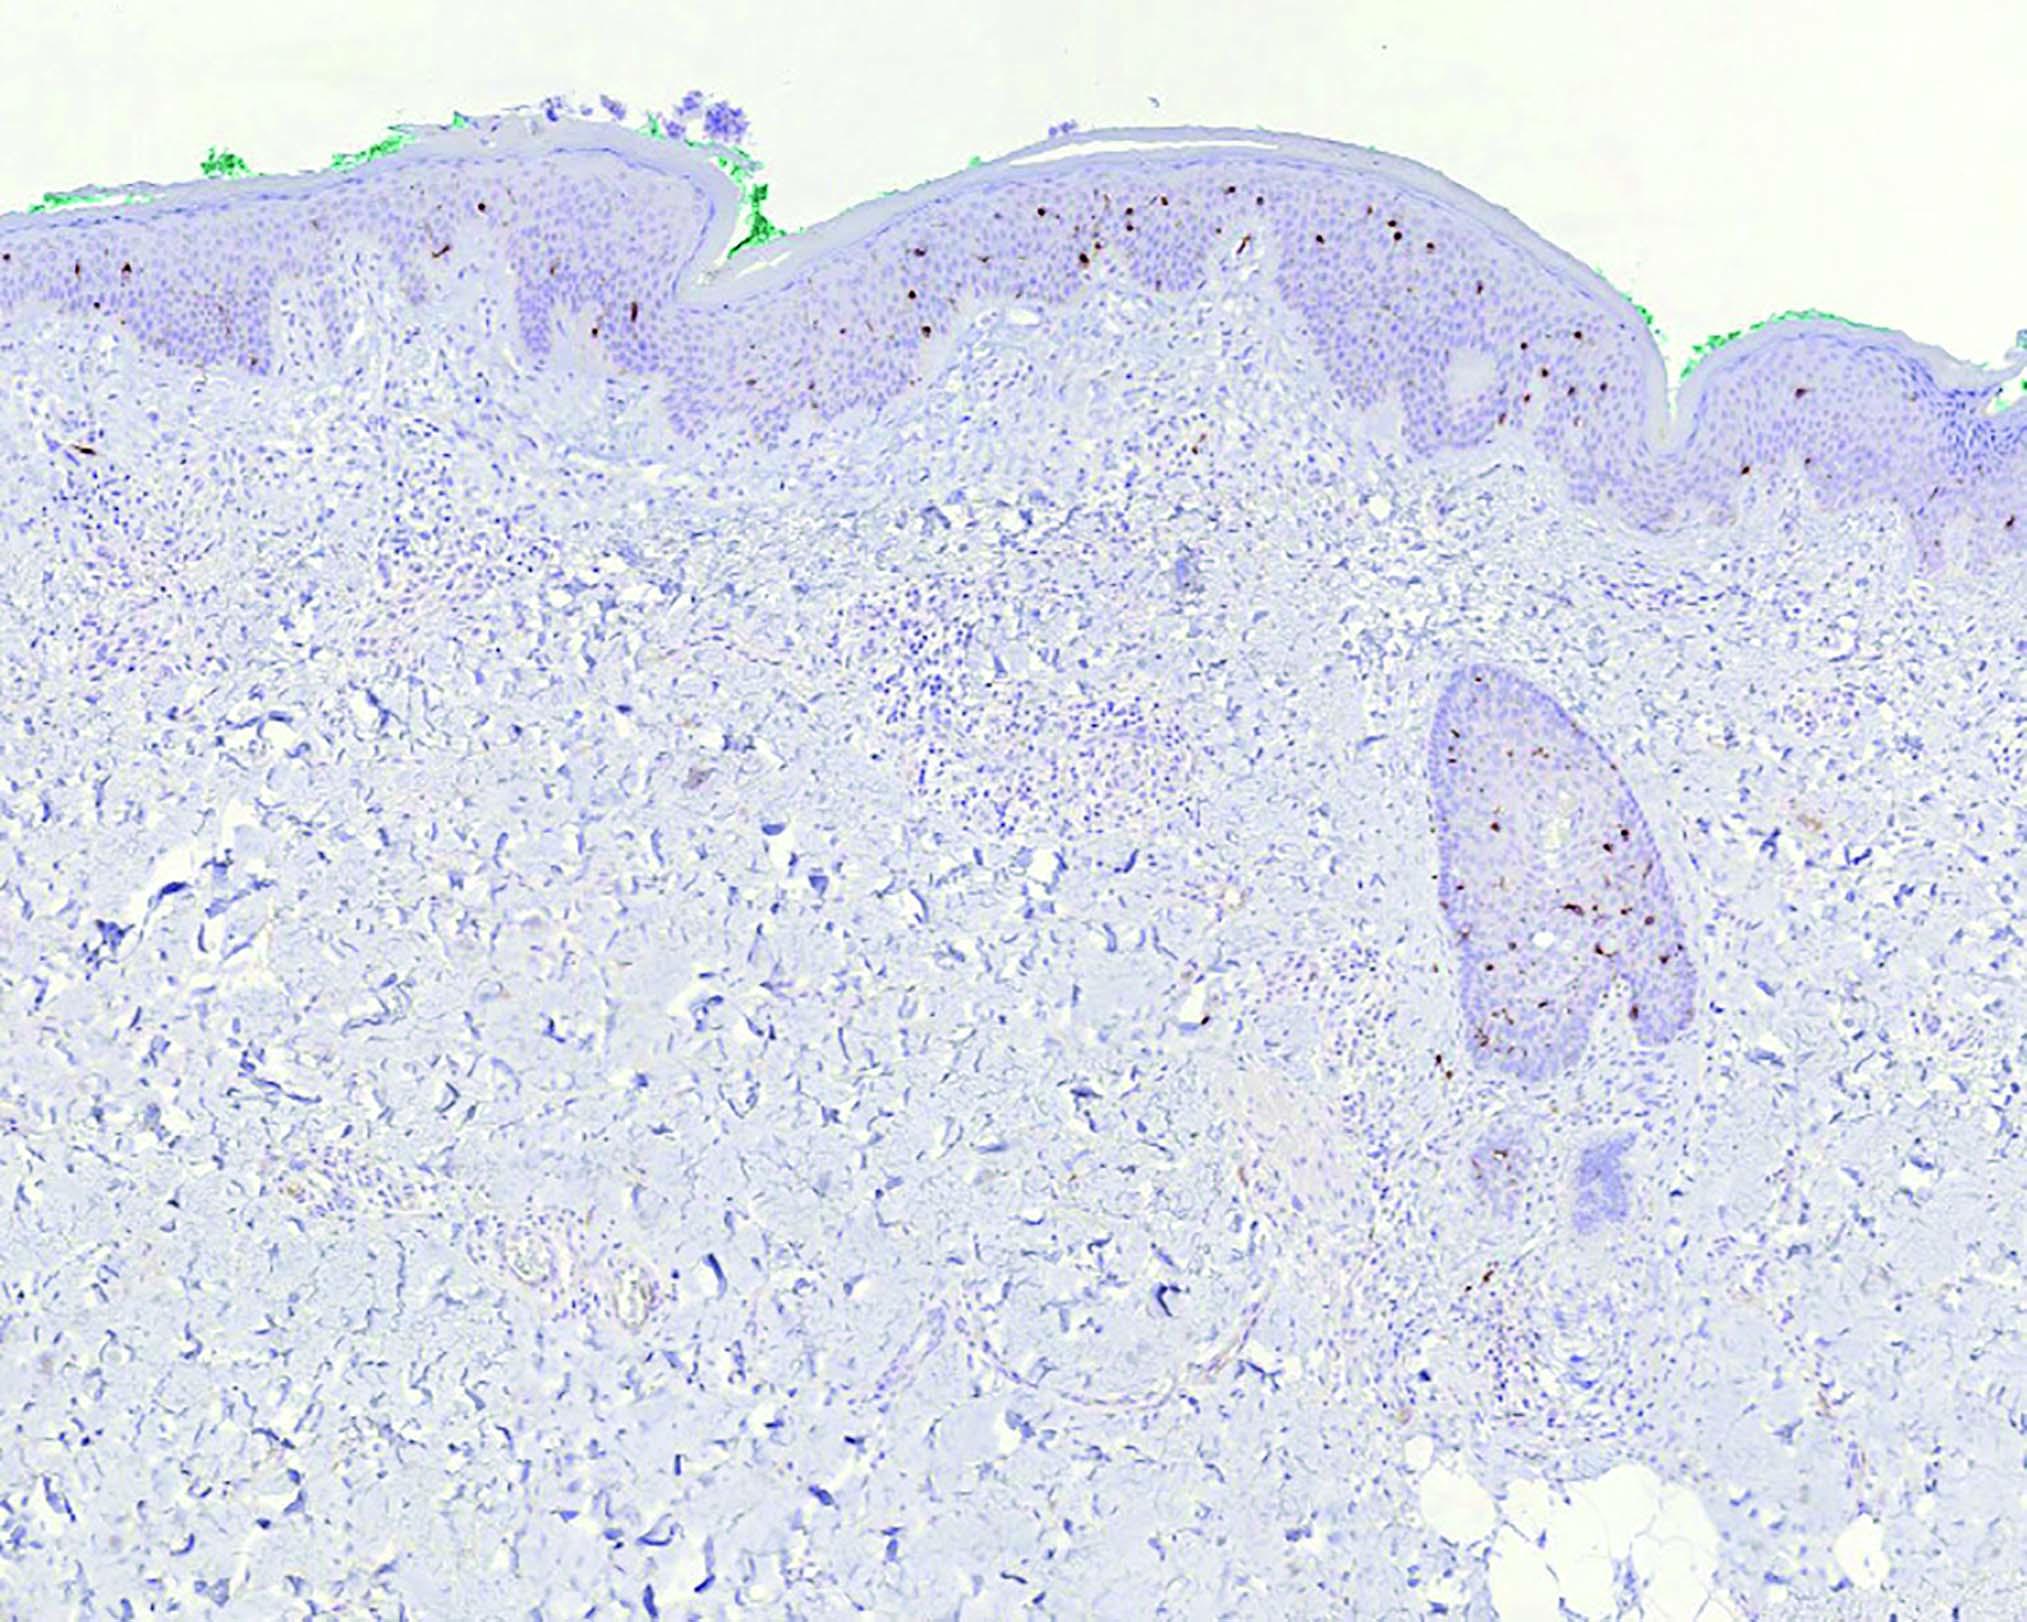

С целью дифференциальной диагностики было проведено иммуногистохимическое исследование, которое показало, что дендритные клетки экспрессируют CD1a, CD4, слабо — белок S100 (рис. 5–7) и не экспрессируют лангерин, CD56, CD68, CD123, CD163, TdT, Cyclin D1, MNDA, ERG (рис. 8). В очаге пролиферации значительно преобладают CD3+ Т-лимфоциты над CD20+ В-лимфоцитами, гистиоциты экспрессируют CD68, CD163, S100, MNDA. В дерме рассеяны немногочисленные тучные клетки (триптаза тучных клеток, CD117).

Рис. 5. Иммуногистохимическое исследование с антителами к CD1а; четко выраженная визуализация CD1а-положительных клеток с типичной локализацией во всех слоях эпидермиса с преимущественной локализацией в шиповатом слое, а также в дерме в окружении сосудов (ув. x100)

Fig. 5. Immunostaining with anti-CD1а antibodies. Immunovisualization of CD1a positive cells through all epidermal layers with more prominent presence in spinous layer as well as in the derma around the vessels, x100